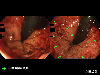

A case of acute hemorrhagic rectal ulcer that was found in an elderly bedridden patient.

Fukuoka Pref., KYUSHU UNIVERSITY HOSPITAL (Dr.Masunari)

Endoscopy